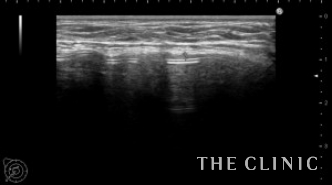

エコーではカプセルの肥厚とカプセル拘縮によるバッグの歪みを認めます。

シリコンバッグによるカプセル拘縮のエコー診断カルテ